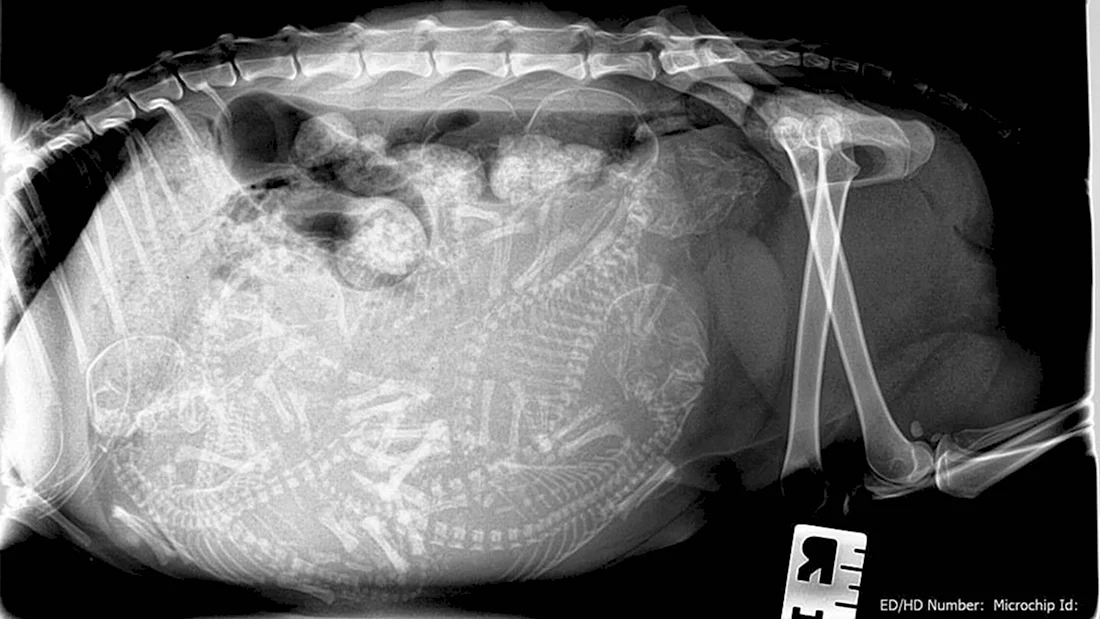

В данной статье представлена уникальная галерея фотографий, которые запечатлевают нежное чудо жизни — котят в утробе кошки. Вас ждут 35 потрясающих фото и картинок, позволяющих заглянуть в мир развивающихся маленьких созданий. Приглашаем вас окунуться в эту удивительную галерею и насладиться прекрасными видами эмбрионов кошачьих детенышей.

Так трогательно и волнующе наблюдать за процессом формирования новой жизни внутри мамы-кошки на этих удивительных фотографиях.